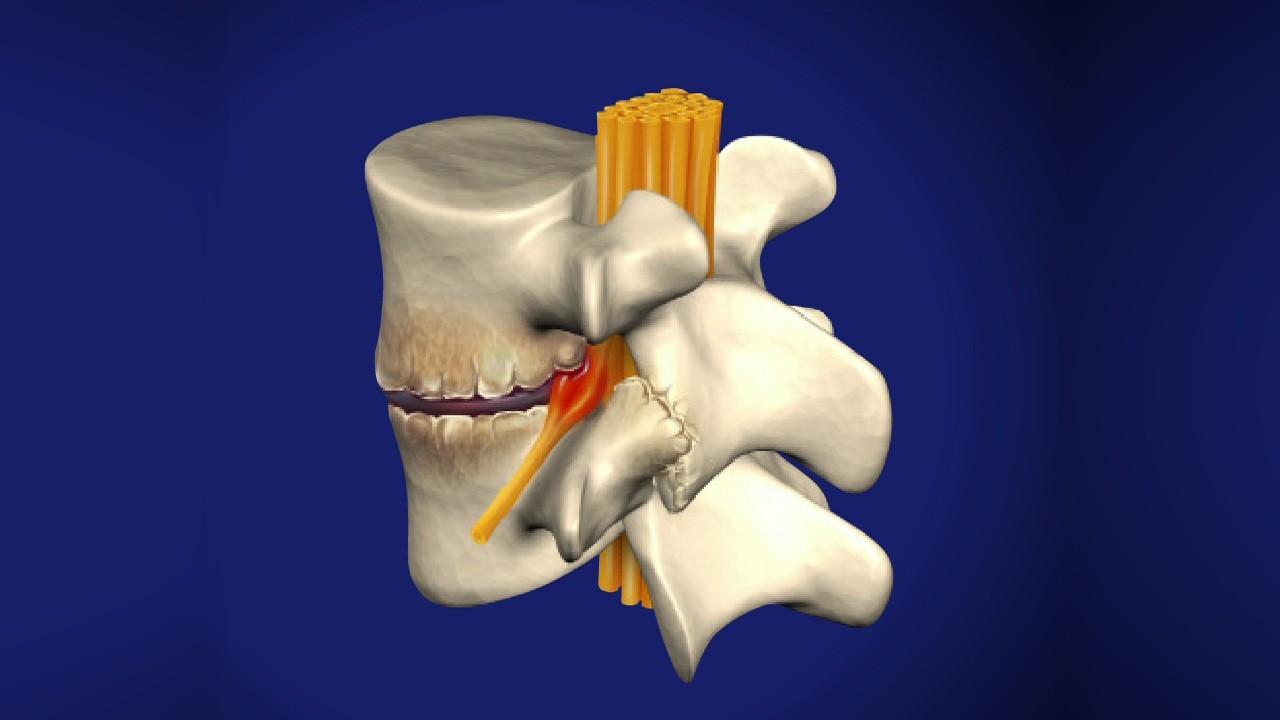

Gai cột sống hay còn gọi là bệnh thoái hóa cột sống là sự hình thành các phần xương mọc ra (gai xương) phía ngoài và hai bên của cột sống. Đây chính là sự phát triển thêm ra của xương trên đốt sống, đĩa sụn, dây chằng quanh khớp do viêm khớp cột sống, chấn thương hoặc sự lắng đọng canxi ở các dây chằng, gân tại đốt sống.

Xương khớp bị viêm: Khi xương khớp bị viêm, đĩa đệm ở giữa các đốt xương bị tổn thương, hư hại. Chính điều này làm mất đi cấu trúc vốn có của cột sống. Khi đó, cơ thể sẽ hình thành gai xương bao quanh khớp xương cột sống để tự ổn định cột sống.

Do bị lắng đọng canxi: Đĩa đệm cột sống bị xẹp đi làm cho dây chằng bị giãn, chuyển động khớp bị ảnh hưởng. Lúc này để giữ vững được cột sống thì cơ thể sẽ tự điều chỉnh để dây chằng dày lên dễ làm gai xương hình thành.

Thoái hóa cột sống: Tình trạng xương cột sống bị thoái hóa có thể dẫn đến gai xương được hình thành. Trường hợp này nếu muốn kiểm soát, loại bỏ được gai xương sống thì cần phải điều trị thoái hóa cột sống.